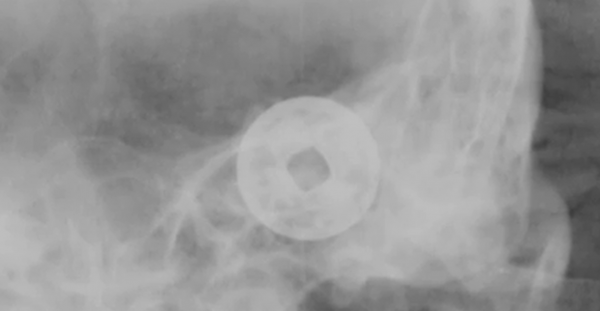

從骨架上來看墓主人並不高,只有一米六左右。當X光照到頭部位置的時候,發現下面有很多枚硬幣,其中在墓主人口中的硬幣比其他硬幣要大。

根據以往的經驗推測,這應該是一枚特製的壓勝錢,在一號棺中也有類似的發現,此時專家們還發現,在墓主人身體多個部位的錢幣連線處,正好是一個北斗七星的圖案。

在X光的照射下,錢幣上的文字也清晰可見,從文字上我們得知墓主人的年代在明代後期,這種奇怪的下葬方式讓考古人員從來都沒有遇到過,當考古人員查閱資料後並沒有找到相關的記載。